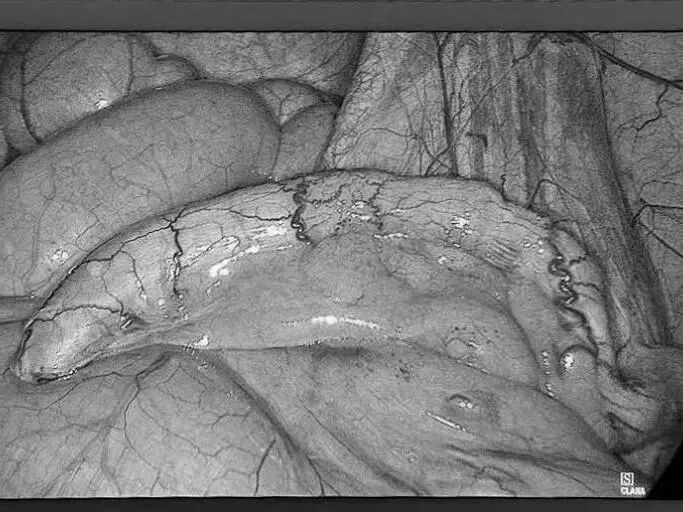

“医生,我爸妈只是关节痛,吃了点止痛药,怎么会胃穿孔要手术?”在普外科病房里,这样的疑问屡见不鲜,很多儿女都困惑不已:明明只是想帮老人缓解疼痛,一片孝心,怎么会把父母送进手术室? 今天,贵州航天医院普外科就来和大家聊聊如何科学、安全地使用止痛药,保护我们脆弱的胃肠,享受健康的生活! 【止痛药咋就把胃吃穿了?】 把胃想象成一个气球,胃黏膜就是内壁,很多止痛药(比如布洛芬、双氯芬酸钠等)会削弱这层内壁,胃酸就像强酸,没了胃黏膜这层内壁保护就会直接腐蚀胃,轻则糜烂、溃疡,重则出血、穿孔。 最危险的是:胃穿孔早期可能只是隐隐作痛、有点胀,容易被当成“老胃病”扛过去,等剧痛发作时,胃里的东西已流进腹腔,危及生命。 【为啥受伤的总是老年人?】 ※胃功能减退:上了年纪,胃黏膜变薄、修复能力下降。 ※多种药同吃:很多老人同时服用降压药、抗凝药,和止痛药叠加,胃根本扛不住。 ※自行用药:怕麻烦不去医院,按老经验或邻居推荐买药,隐患最大。 【安全用药“四要、四不要”】 四要—— ✔要查明原因:疼痛是警报,先看病再吃药,别盲目止痛。 ✔要保护胃:在医生指导下可加用胃黏膜保护剂(如奥美拉唑)。 ✔要饭后吃:务必饭后半小时服用,减少刺激。 ✔要见好就收:不疼了就停药,绝不长期吃。 四不要—— ❌不要自己加量:疼得厉害?找医生,别加药。 ❌不要混着吃:不同止痛药一起吃等于伤害叠加。 ❌不要长期吃:一般疼痛不连续吃超过一周。 ❌不要忽视警报:出现胃部不适、黑便、呕血、剧烈腹痛,立即停药就医! 【对付慢性疼痛,还有其他好办法】 ▶热敷、冷敷:简单有效,很多肌肉关节痛都管用。 ▶理疗、按摩:找正规中医推拿,效果不输止痛药。 ▶温和运动:散步、打太极,增强肌肉力量。 ▶转移注意力:养花、写字、聊天——当你不那么关注“痛”时,痛感往往会减轻。 【给子女的2点提醒】 ※管好药箱:定期清理过期药,搞清楚老人每天在吃什么药。 ※当好翻译:陪老人看病时,说清哪里痛、吃过啥药、效果如何。 止痛药是缓解疼痛的有效工具,但绝非“万能神药”。请一定记住:面对疼痛,“硬扛”不是办法,“乱吃”更是大忌,守护胃肠健康,从科学用药开始。 注:本文仅为健康科普,旨在提高公众用药安全意识,具体用药请务必咨询专业医生,遵医嘱执行。 贵州航天医院普外科专家简介 高大勇 普外科(肛肠外科)学科带头人、名誉主任,主任医师、教授 临床擅长:对中西医结合诊治肛肠学科各种常见病、多发病及疑难杂症等具有丰富的临床经验。 原遵义市第一人民医院(遵义医科大学第三附属医院)、遵义市中医院肛肠科主任。中华中医药学会肛肠分会常委,全国中医肛肠学科名专家,中国健康促进与教育协会肛肠分会常委,中国康复医学会肛肠疾病康复专业委员会常委,中国民间中医医药研究开发协会肛肠分会副秘书长,中国医师协会中西医结合肛肠医师专业委员会常委,国家二级心理咨询师,贵州省第一批中医名医工作指导老师,遵义市名中医,遵义市肛肠学会会长,遵义市肛肠质控中心名誉主任,遵义市中西医结合学会名誉会长,遵义市健康科普专家,原贵州省中西医结合学会肛肠分会副主任委员、贵州省中医肛肠质控中心副主任、遵义市医学会医疗鉴定委员会专家、遵义市卫生系列高评委。发表论文30余篇,主编和参编医学著作5本,主持省级科研课题2项、市级科研课题2项、院级科研课题1项。 梁 跃 普外科党支部书记、主任,主任医师 临床擅长:对普外科各类肿瘤手术具有丰富的临床经验。 毕业于遵义医学院,遵义市医学会小儿外科学分会常务委员,遵义市肛肠协会理事,遵义市医学会核医学分会(第二届)委员会委员;荣获第三期“黔医人才计划”优秀学员称号;主持市级课题1项,完成省级课题1项,在国内各类刊物上发表论文10余篇。 钱科洪 民盟盟员,普外科副主任医师 临床擅长:从事普外科临床工作30余年,对各类普外科疾病的诊治、乳腺、甲状腺、胃十二指肠、结直肠等疾病及疑难杂症具有丰富的临床经验。 毕业于遵义医学院临床医疗系,2009年前往中山大学附属第一医院微创外科进修学习,在国内各专业期刊发表论文数篇。 贵州航天医院普外科简介 基本情况 贵州航天医院普外科成立于1968年,前身属于航天部O61基地3417医院外一科,1998年3417医院、3427医院合并后更名为普外科,下设胃肠外科、肛肠外科2个亚专业科室,拥有在全市较为先进的专科设备和技术,是中国疝病专科联盟单位,贵州医科大学附属医院胃肠外科专科联盟单位。开放床位40张,配备医护人员21人。 专科特色 普外科致力于胃肠及肛肠疾病的外科临床诊治及科研,以腹腔镜微创外科技术为本,形成以快速康复治疗胃肿瘤、结直肠肿瘤、小肠肿瘤、直肠脱垂、肥胖病、急腹症、各类疝、痔、瘘等专科特色,同时注重胃肠疾病尤其是结直肠恶性肿瘤的基础研究和临床转化研究,总体诊断和治疗水平在区域同级医院居于领先水平。 开展手术:腹腔镜下胃癌根治术,腹腔镜下袖状胃切除术,腹腔镜下胃肠道间质瘤切除术,腹腔镜下结、直肠癌根治术,胃癌、结直肠癌的精准治疗,腹腔镜下小儿疝气、成人疝修补术,腹腔镜下阑尾手术,内痔的硬化注射治疗及痔疮的微创治疗:ATH、PPH、TST,直肠脱垂的各种手术治疗,难治性伤口VSD技术,鼻胃肠管、肠梗阻导管置入术,肛肠术后间歇性导尿技术,并引进了中医适宜技术,也为各种化疗患者提供输液港安装,提高患者就医体验。 腹腔镜下腹股沟疝 无张力修补术 腹股沟疝里金斯坦 (Lichtenstein)手术 PPH微创术治疗环状混合痔 黏连性或炎性肠梗阻-肠梗阻导管 腹腔镜袖状胃切除 腹腔镜阑尾切除术 腹腔镜阑尾肿瘤切除术 腹腔镜下结肠癌根治术 诊疗范围 胃肿瘤、结直肠肿瘤、小肠肿瘤、肥胖症、各类急腹症、腹部外伤、腹壁疝、便秘、直肠脱垂、痔疮、肛瘘、肛裂等胃肠、肛肠外科疾病。 END